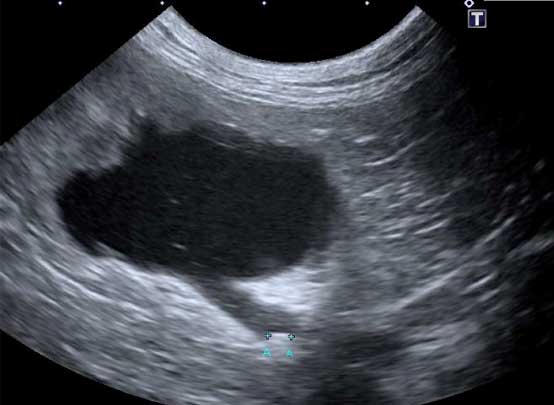

超音波検査

腎臓や膀胱の内部構造を確認します。腎臓においては形態や構造の変化、血流の評価を、膀胱においては壁の厚さや不整、内部の結石や血餅などの評価を行います。その他にも、尿管や尿道、雌では子宮や卵巣、雄は前立腺の評価にも有用です。

超音波腎臓

超音波膀胱